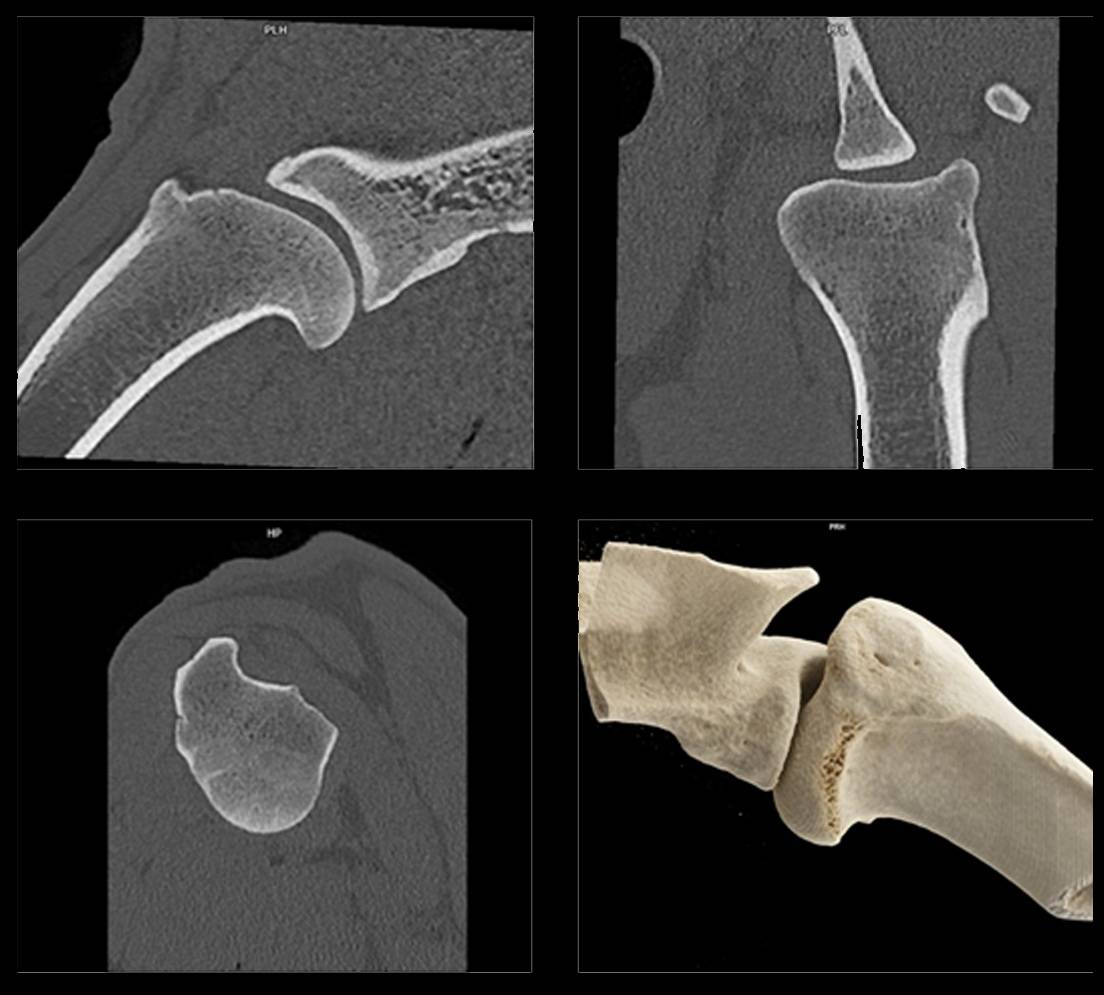

Loket byl rozsáhle studován pomocí CT. CT vyšetření lokte je obzvláště cenné při definování různých patologií spojených s dysplazií lokte a plánováním chirurgických zákroků. Prosté rentgenové vyšetření, ačkoli je schopno posoudit většinu změn spojených s dysplazií lokte, nemůže spolehlivě určit přítomnost fragmentovaného mediálního korunního výběžku nebo stupeň inkongruence kloubu, což je snadno viditelné pomocí CT.

V celkové anestezii je pacient uložen do sternální polohy vleže a přední končetiny jsou co nejvíce kraniálně nataženy. Oba lokty lze zobrazit ve stejné rovině skenování a pokud jsou symetricky umístěny, lze je snadno porovnat během prohlížení snímků. Axiální snímky se získávají z distálního humeru přes proximální radius a ulnu. Překrytí axiálních řezů umožňuje lepší rekonstrukci do dorzálních a sagitálních snímků. Sagitální rekonstrukce snímků umožňuje nejlepší posouzení inkongruence kloubů.

Mediální korunní výběžek (MCP) by měl být posouzen z hlediska fragmentace nebo fisur, velikosti a tvaru, tvorby osteofytů a sklerózy.

Mezi další důležité oblasti zájmu patří humeroulnární, humeroradiální a radioulnární spojení (kongruence kloubu), vyšetření humerálního kondylu z hlediska subchondrální kostní lýzy a sklerózy, které svědčí o osteochondróze, a mediální a laterální kolaterální kostní a měkké tkáně.

V procesu vyšetření může pomoci zobrazit anatomické oblasti zapojené do dysplazie lokte. Patří mezi ně: mediální a laterální epikondylární kostní reakce, kostní reakce háčkovitého výběžku proximálně, nesrůstající háčkovitý výběžek, nesouběžnost kloubu, remodelace MCP, osteofytóza hlavice radia a skleróza trochleárního zářezu ulny.